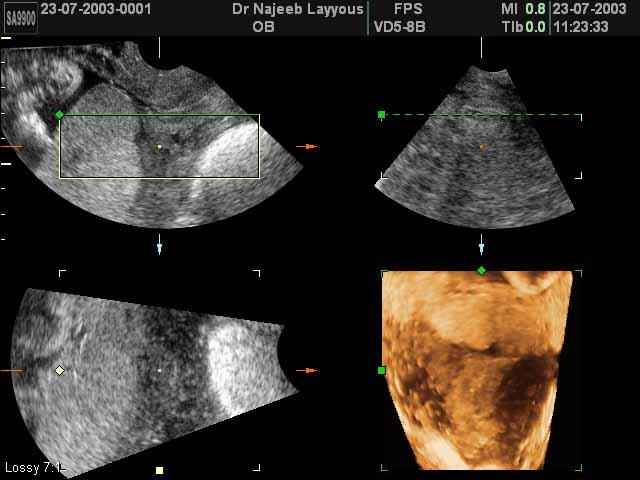

- The Clinical Advantages of 3D and 4D Ultrasound

- Definition and Features of Four Dimensional Ultrasound

- Uses of 4D Ultrasound scan

- Second Trimester Ultrasound Photos

- Pregnancy Ultrasound Photos For Obstetricians